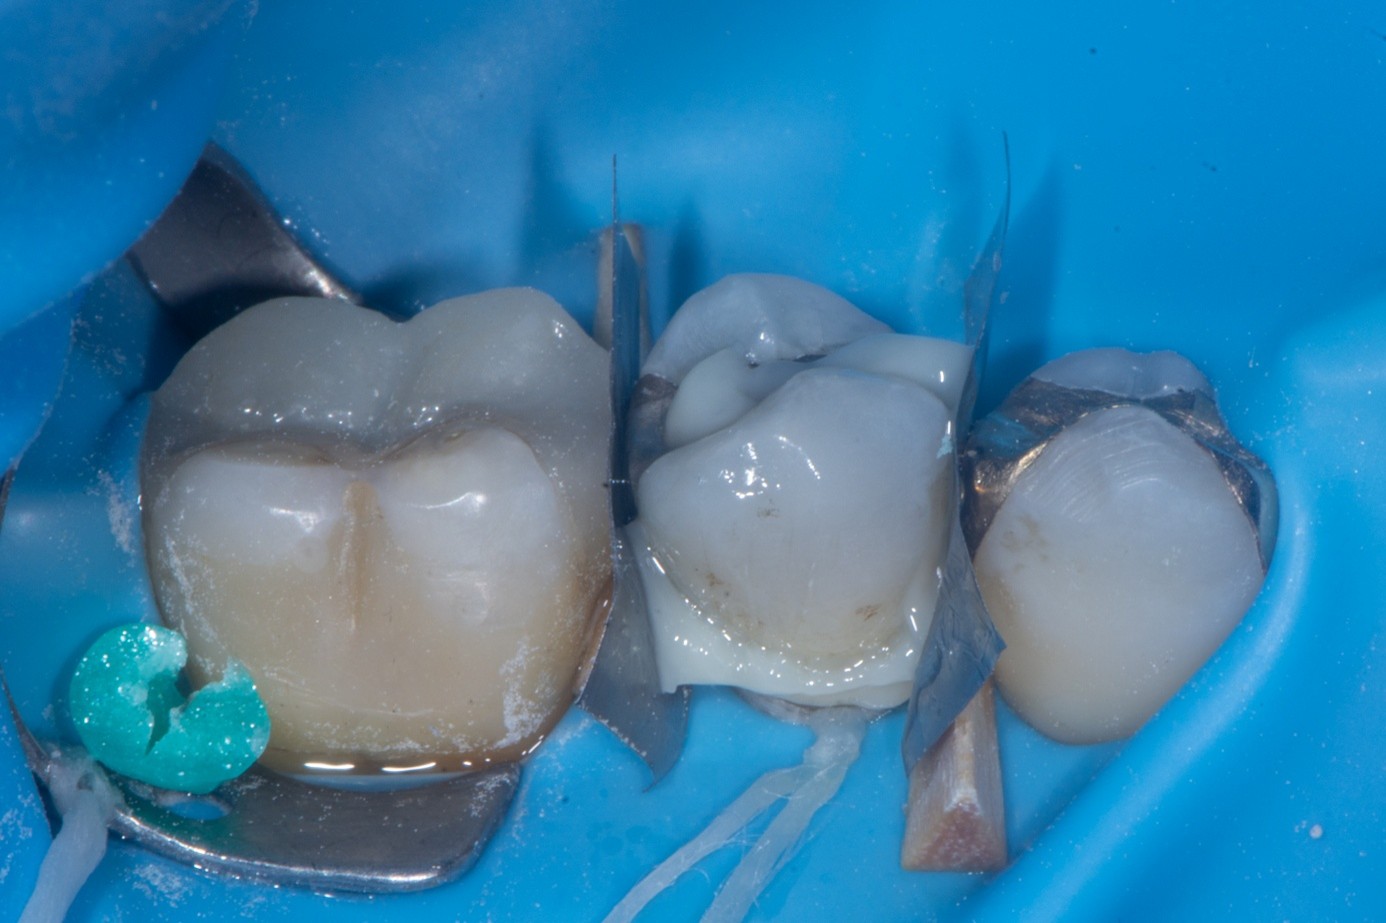

Case 4: Fractured Cusp

A patient presented on an urgent basis with a fractured buccal cusp of the mandibular second premolar (Figure 32). The tooth had a large MOD amalgam restoration, and the patient fortunately brought the fractured cusp fragment with them. Cuspal fractures of this type are common in teeth restored with amalgam or in teeth with thin, unsupported cusps under bonded restorations. Over time, occlusal forces flex the cusps, leading to crack initiation along the stress plane until catastrophic fracture occurs.

Clinical Procedure

After verifying the fit of the fractured cusp, three-tooth rubber dam isolation was achieved (first premolar to first molar). Dentin adjacent to the fracture line was protected with liquid dam to prevent contamination during amalgam surface preparation (Figure 33). The existing amalgam restoration and fractured surfaces were air-abraded with 27-μm aluminum oxide particles, which effectively cleansed the surface and created micromechanical retention. Care was taken to avoid excessive abrasion of exposed dentin to prevent unnecessary loss of tissue.

The enamel margins were etched with phosphoric acid, rinsed, and dried (Figure 34). A primer and adhesive were applied to both the tooth and the cusp fragment but were left unpolymerized at this stage to allow for chemical coupling (Figure 35 and Figure 36). A layer of heated packable composite resin was applied to the fractured interface, and the cusp was carefully repositioned in its original place. Excess adhesive and composite were removed with a microbrush, and the restoration was light-cured thoroughly from multiple angles.

(32.) Intraoral view showing a fractured buccal cusp of the mandibular second premolar.

Figure 32

(33.) Amalgam surface prepared for sandblasting to improve mechanical retention. The adjacent dentin is protected with liquid dam to prevent contamination by amalgam particles, which could otherwise cause staining and interfere with hybrid layer formation.

Figure 33

(34.) Application of the selective etching technique, with phosphoric acid applied only to the enamel surface, leaving the dentin unetched.

Figure 34

(35.) Inner surface of the fractured cusp after sandblasting and enamel etching, showing amalgam staining and small cracks, now prepared for adhesive reattachment.

Figure 35

(36.) Inner surface of the fractured cusp after sandblasting and enamel etching, showing amalgam staining and small cracks, now prepared for adhesive reattachment.

Figure 36